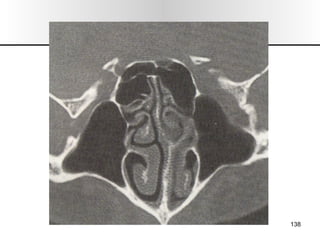

EXPLORACION 1.- Inspección/ Palpación:  Forma, color, alt. Dermicas, movilidad, dolor, inspiración forzada (colapso alar). 2.- Rinoscopia Ant: Desvios, esporones, cornetes, polipos  (solitario),  secreciones, perforaciones, CE, tumores. 3.- Rinoscopia Post: Hipertrofia cornetes, tumores. 4.- Tacto de Cavum: Adenoides. 5.- Rinonanometria: Dif de presión entre vestíbulo y coanas, flujo de vol. 6.- Exp. Radiológica : mentonasoplaca, frontonasoplaca, perfil, axial de Hirtz o submentovertex. TAC, RMN. 7.- Endoscopia Rinusinusal. 8.- Pruebas Alergologicas: pruebas cutaneas, eosinofilia, exudado nasal. SEMIOLOGIA

EXPLORACION 1.- Inspección/Palpación: Forma, color, alt. Dermicas, movilidad, dolor, inspiración forzada (colapso alar). 2.- Rinoscopia Ant: Desvios, esporones, cornetes, polipos (solitario), secreciones, perforaciones, CE, tumores. 3.- Rinoscopia Post: Hipertrofia cornetes, tumores. 4.- Tacto de Cavum: Adenoides. 5.- Rinonanometria: Dif de presión entre vestíbulo y coanas, flujo de vol. 6.- Exp. Radiológica : mentonasoplaca, frontonasoplaca, perfil, axial de Hirtz o submentovertex. TAC, RMN. 7.- Endoscopia Rinusinusal. 8.- Pruebas Alergologicas: pruebas cutaneas, eosinofilia, exudado nasal. SEMIOLOGIA